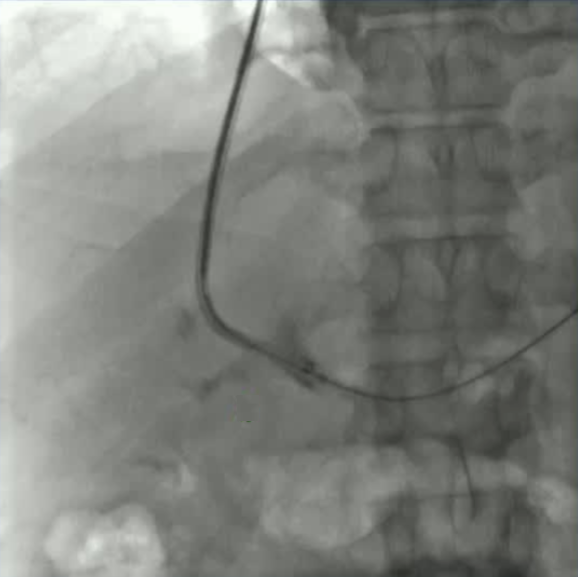

该程序包含以下步骤: 经脾脏入路:在超声引导下,刺穿脾静脉内的一个实质内分支。 在通过脾静脉造影确认了静脉通路后,导管和导丝被推进,以穿过脾静脉并抵达血栓化的门静脉。在门静脉/右门静脉分支处放置圈套器,为TIPS穿刺精准定位。TIPS穿刺圈套器,并穿过圈套器完成TIPS

步骤: 鉴于慢性血栓形成的复杂性: 一种经脾脏途径的门静脉再通术(PVR)。 随后是经颈静脉肝内门体分流术 。